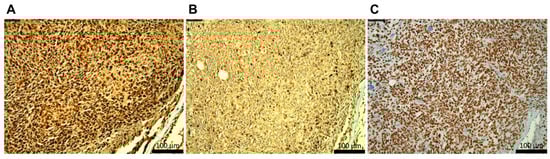

Ewing sarcoma (ES) is the second most common primary bone malignancy in children and adolescents and remains one of the most lethal pediatric cancers. Found in more than 85% of patients with ES, EWSR1::FLI1 results from the t(11;22)(q24;q12) chromosomal translocation. This fusion encodes an aberrant transcription factor that dysregulates gene expression and drives oncogenic transformation. Although this oncogene was identified over three decades ago, therapeutic progress has been limited, in part due to the lack of robust and permissive animal models. Prior efforts to generate transgenic mouse models have been unsuccessful, and while zebrafish have emerged as a promising system, a tissue context capable of supporting EWSR1::FLI1-driven tumorigenesis has not been defined. Here, we report that tissue-specific expression of EWSR1::FLI1 in zebrafish induces tumor formation that recapitulates the histologic and molecular hallmarks of human ES, including small round blue cell morphology and characteristic biomarker expression. Tumors were driven by the col2a1a promoter and resulted in ~70% incidence of notochord tumors within the first 72–96 h. Of the surviving fish, ~5% developed CD99-positive small round blue cell tumors at ~9 months post-fertilization. This work establishes a stable tissue-specific transgenic model of ES, providing a powerful in vivo platform to investigate disease pathogenesis and evaluate novel therapeutic strategies. Full article